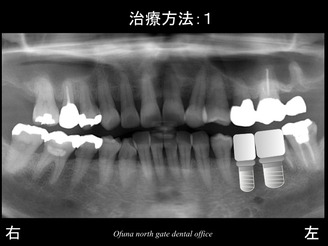

早速初診時のレントゲンから始めましょう!

初診時、下顎左側の奥歯が欠損しているため、治療法を聞きたく来院されました。

このようなケースが最も多いです。

このような症例の場合、どのような治療方法があるのでしょうか?

そして、インプラントを2本埋入するのです。

これが最も将来性が高い治療と言えます。